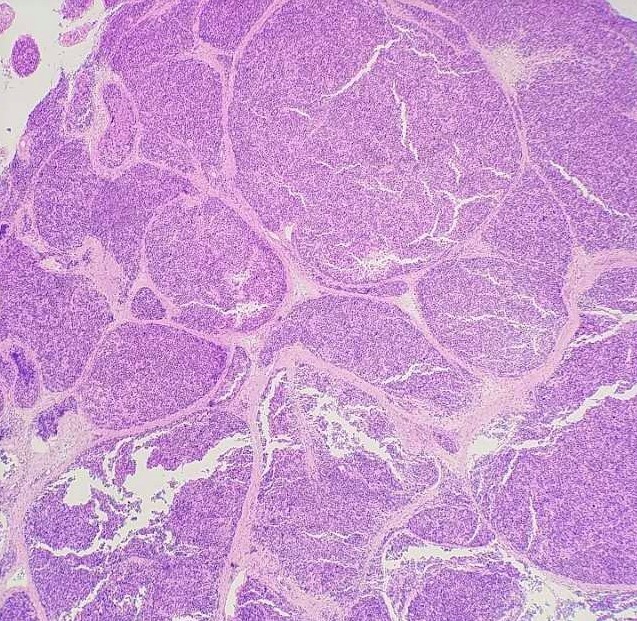

Spermatocytic tumor is a rare germ cell tumor (1-2%) with an average patient age of 55 but does occur in younger individuals such as in this case. Patients often present with testicular swelling with mass. Serum tumor markers are generally not elevated. Macroscopically, these tumors appear as a well-circumscribed tan-grey mass with a bulging surface. Microscopically, these tumors demonstrate a diffuse or sheet-like pattern with edematous stroma and separation by fibrous bands. The tumor is comprised of a polymorphous cell population comprised of 3 main cell types: Small lymphocyte-like cells, intermediate cells and giant cells. Germ cell neoplasia is usually not associated with spermatocytic tumors. The tumor cells are positive for SALL4, CD117, OCT2, CAM 5.2 (40%), and negative for CD30, PLAP, AFP, OCT3/4, D2-40, Glypican-3, EMA, CD30 and Vimentin. The differential diagnosis includes seminoma, embryonal carcinoma (solid pattern) and malignant lymphoma. Radical inguinal orchiectomy is curative with an excellent prognosis.